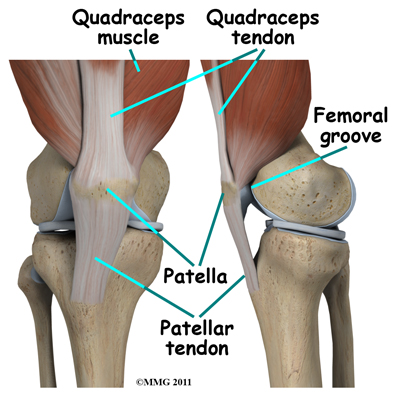

The knee joint is formed where the femur (lower end of the thighbone) connects with the tibia (upper end of the main lower leg bone). On the front of the joint is the patella (kneecap). The patella is what is called a sesamoid bone that is a part of the extensor mechanism of the knee joint. The extensor mechanism connects the large muscles of the thigh to the tibia such that contracting the thigh muscles pulls on the tibia and allows us to straighten the knee. The parts of the extensor mechanism include the thigh muscles, the quadriceps tendon, the patella and the patellar tendon.

The knee joint is formed where the femur (lower end of the thighbone) connects with the tibia (upper end of the main lower leg bone). On the front of the joint is the patella (kneecap). The patella is what is called a sesamoid bone that is a part of the extensor mechanism of the knee joint. The extensor mechanism connects the large muscles of the thigh to the tibia such that contracting the thigh muscles pulls on the tibia and allows us to straighten the knee. The parts of the extensor mechanism include the thigh muscles, the quadriceps tendon, the patella and the patellar tendon.